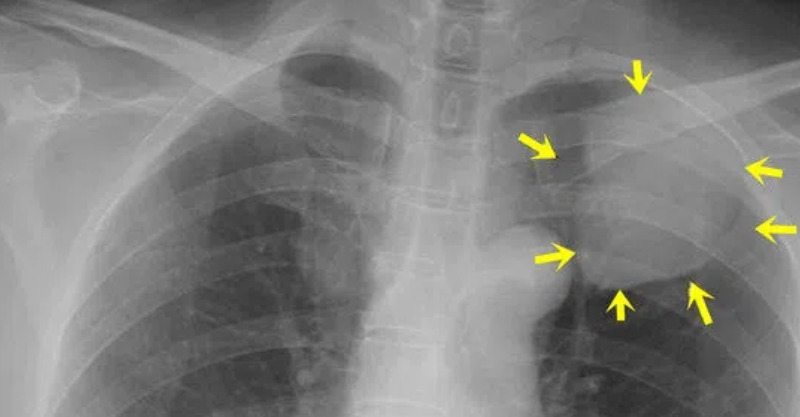

根據《TVBS》報導,大陸一名母親某天發現兒子的鎖骨上有堅硬腫塊,然而卻不痛不癢,隨後送往醫院檢查驚覺確診「肺癌」且已是晚期,醫師替男童鎖骨上的腫塊進行「部分切除活檢術」,術後報告顯示為「尤文氏肉瘤(Ewing's sarcoma)」也就是未分化的網狀細胞瘤。

但母親不放心又再帶去另一間醫院檢查,結果竟然確診為肺癌晚期,且因腫瘤惡性度高,要康復相當困難。父母得知到不敢置信孩子小小年紀竟然罹肺癌還是晚期,崩潰的說「兒子『沒什麼吃過早餐』,中晚餐也是他們追著餵才吃上半碗飯。『白開水』基本上也都不喝,渴了就喝果汁、飲料。」此外,兒子還特別喜歡打電動,有次趁著父母睡著偷偷拿手機玩,導致「常熬夜、生活作息不規律」。